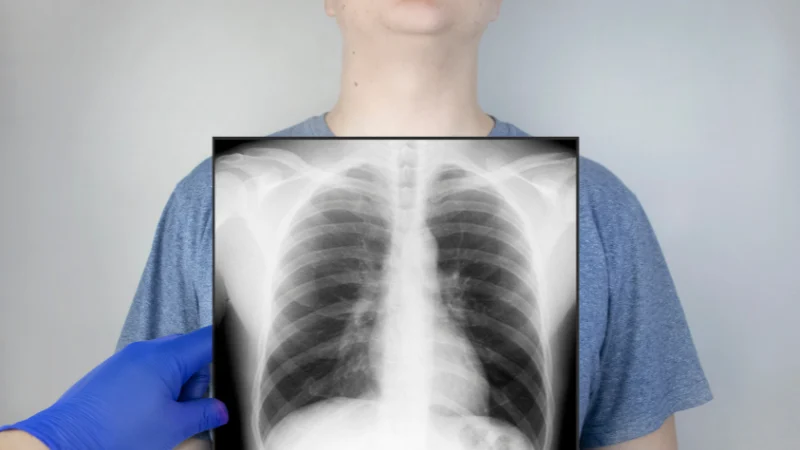

O exame físico (frequência respiratória, ausculta pulmonar e saturação de oxigênio) e exames de imagem (RX ou tomografia de tórax) podem ajudar nesse diagnóstico.